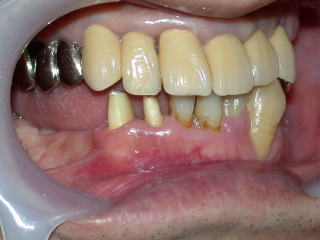

抜歯した穴も十分治り、仮歯、インプラント植立の固定用仮歯の用意もでき、次回インプラント植立します。

患者さんの希望により全部セラミックスの白い歯を入れることになりました。

インプラント植立費用150.000円とセラミックス5本(87.000円×5本)で

合計585.000円(消費税は不要です)の予定です。